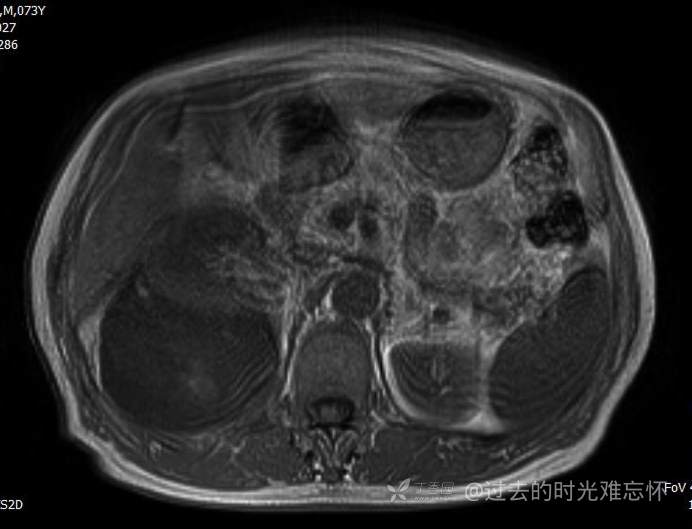

T2压脂

患者性别:男

患者年龄:73岁

主诉:咳嗽1月余。曾有血尿一次。后背部酸痛不适1-2年左右,无明显消瘦。

辅助检查:CT MRI

临床诊断:占位

黏液样脂肪肉瘤 (12)